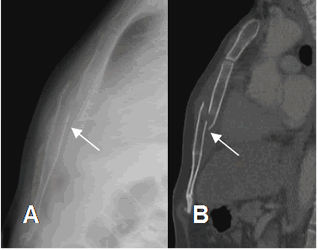

Fig 29. Fractura del esternón.

A: Rx lateral y B: TAC reconstrucción sagital. Fractura en sentido oblicuo y poco desplazada, del cuerpo esternal.